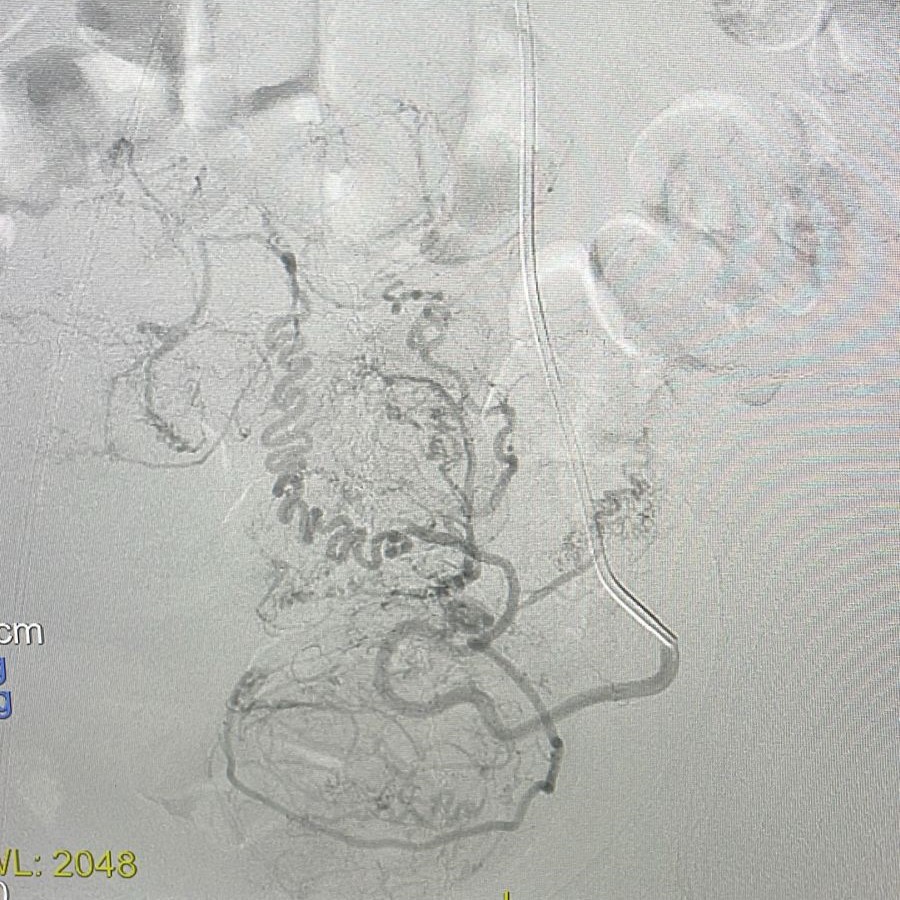

A equipe do Hospital Vaz Monteiro inovou novamente ao realizar, pela primeira vez na região, uma embolização de miomas uterinos, procedimento minimamente invasivo, com punção arterial e cateterização seletiva dos ramos uterinos tanto do lado direito quanto do lado esquerdo, visando administração de embosferas.

De acordo com Dr. Dirceu Dias Barbosa Sobrinho, coordenador da Divisão de Hemodinâmica do hospital, as embosferas são “estruturas desenvolvidas para interromper o fluxo arterial aos miomas, ocasionando sua regressão e desaparecimento, já que os tumores deixam de receber fluxo sanguíneo”.

A embolização foi realizada em uma paciente de 46 anos que buscou tratamento devido a sintomas de dores abdominais do tipo cólicas intensas, frequentes e com sangramentos aumentados, além de dores e sensação de pressão na bexiga.

Havia duas opções no caso: a Histerectomia (retirada total do útero por via abdominal ou pélvica) ou a Embolização. Como não desejava se submeter à histerectomia, a paciente foi encaminhada ao serviço de Hemodinâmica do Vaz Monteiro para avaliação da possibilidade de embolização do mioma. “Felizmente, a ressonância magnética da pelve indicou que se tratava de miomas do tipo subseroso, que respondem muito bem à técnica de embolização”, explica Dr. Dirceu.